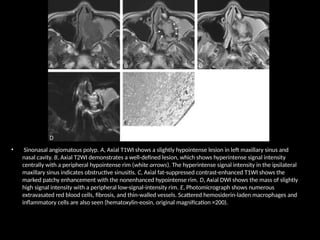

• Sinonasal angiomatous polyp. A, Axial T1WI shows a slightly hypointense lesion in left maxillary sinus and

nasal cavity. B, Axial T2WI demonstrates a well-defined lesion, which shows hyperintense signal intensity

centrally with a peripheral hypointense rim (white arrows). The hyperintense signal intensity in the ipsilateral

maxillary sinus indicates obstructive sinusitis. C, Axial fat-suppressed contrast-enhanced T1WI shows the

marked patchy enhancement with the nonenhanced hypointense rim. D, Axial DWI shows the mass of slightly

high signal intensity with a peripheral low-signal-intensity rim. E, Photomicrograph shows numerous

extravasated red blood cells, fibrosis, and thin-walled vessels. Scattered hemosiderin-laden macrophages and

inflammatory cells are also seen (hematoxylin-eosin, original magnification ×200).